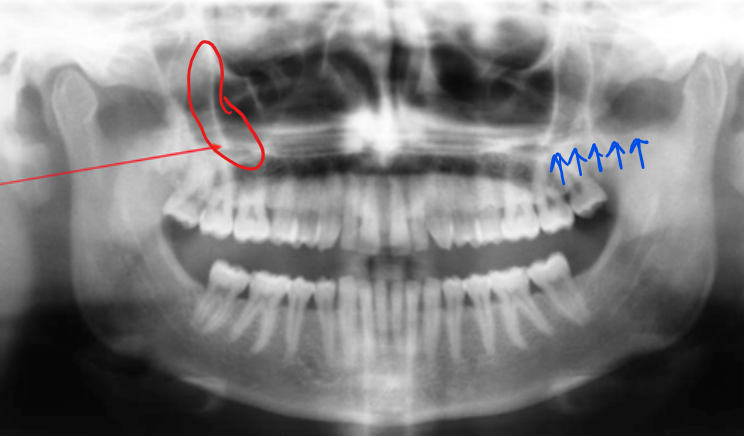

ear

in the circle, indicated by the arrow

styloid process

red - zygomatic process of maxilla

blue - zygoma